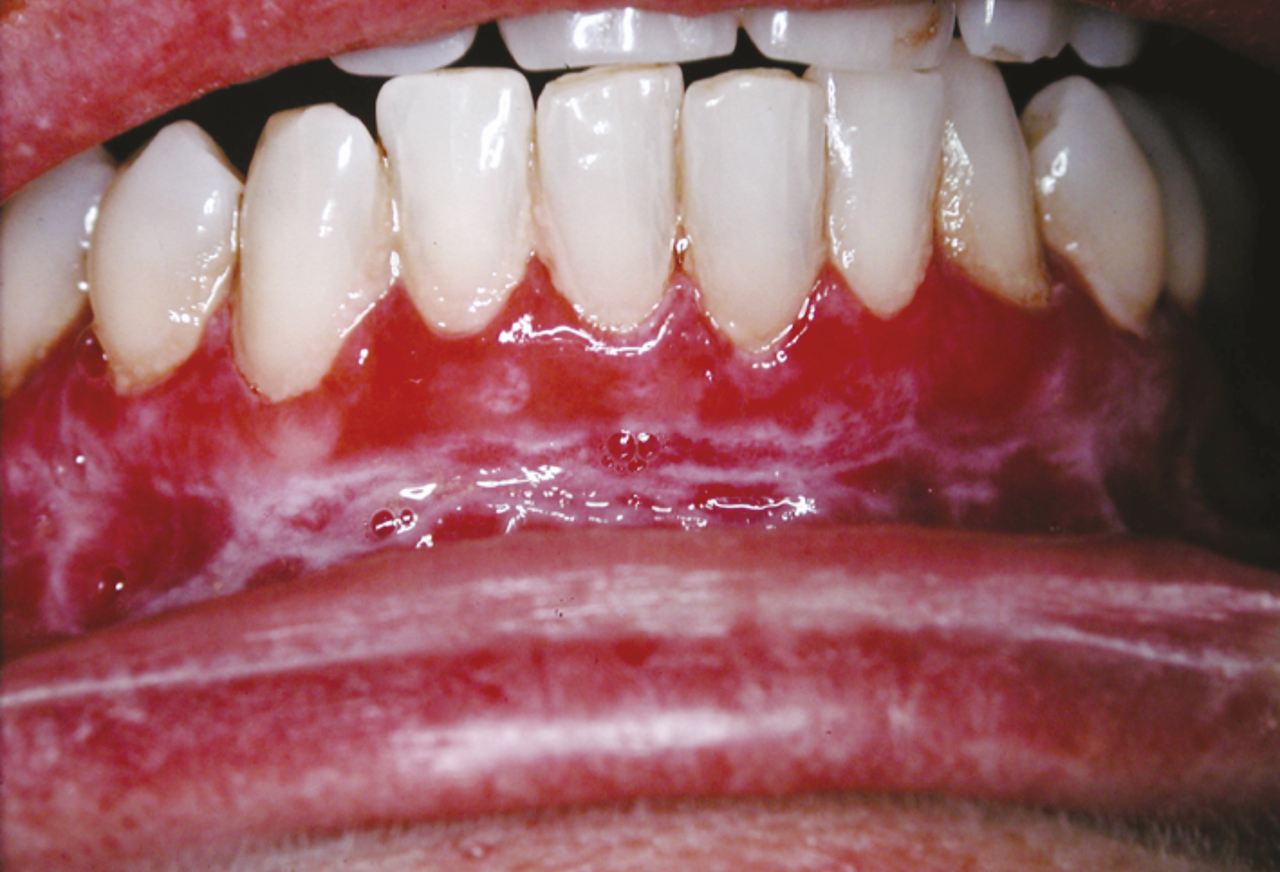

L’érythroplasie de la muqueuse buccale est toujours considérée comme la lésion au potentiel de transformation maligne le plus élevé. Certains auteurs ne la considèrent plus comme une lésion potentiellement maligne dans la mesure où le cancer est déjà présent dans la grande majorité des cas. L’érythroplasie est une plage veloutée, rouge brillant, le plus souvent uniforme sans trace de kératinisation, souvent très étendue mais ayant une limite nette (fig. 3 ), ce qui la distingue des érythèmes inflammatoires. Le diagnostic d’érythroplasie est un diagnostic d’élimination de toutes les autres causes possibles de plages érythémateuses de la muqueuse buccale : dermatoses telles que le lichen plan érythémateux, le lupus ou la pemphigoïde cicatricielle, le syndrome de Reiter, les infections bactériennes ou mycosiques chroniques (candidoses, histoplasmose), les réactions à des agressions physiques ou chimiques, les réactions immunitaires d’hypersensibilité, les plages érythémateuses symptomatiques d’une anémie, les hémangiomes ou les lésions débutantes de maladie de Kaposi.

– la forme érosive, la plus fréquente, associe à un fond érythémateux des zones érosives douloureuses à limites nettes, à fond le plus souvent rouge (fig. 6 ). L’érosion peut laisser la place à une véritable ulcération avec un fond fibrineux. La présence d’un réseau lichénien en périphérie de ces lésions confirme le diagnostic. L’aspect, lorsqu’il concerne les gencives, peut être fait de lésions classiques de lichen (fig. 7 ) ou devenir celui d’une gingivite érosive et desquamative (fig. 8 ), et le diagnostic différentiel est alors difficile avec les affections bulleuses de la muqueuse orale. Les formes atrophiques s’observent plus volontiers sur la gencive, le dos de la langue où elles s’accompagnent d’une dépapillation irréversible. Les patients se plaignent d’une sensibilité accrue aux aliments épicés ou d’une irritation liée au brossage des dents.

– la forme érosive, la plus fréquente, associe à un fond érythémateux des zones érosives douloureuses à limites nettes, à fond le plus souvent rouge (